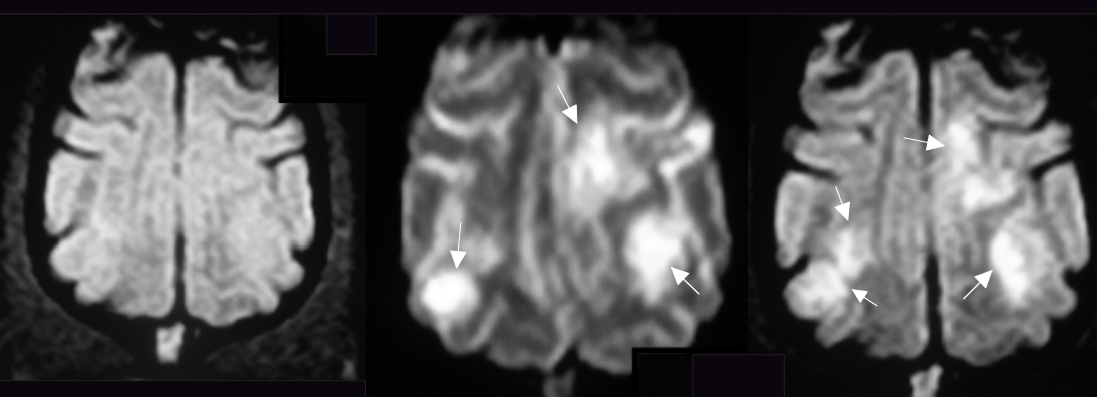

| Brain CT |

![]() |

| ๋ ์์์ multifocal ์ผ์ฆ ์๊ฒฌ (์๋, ์ค๋, ๋์ค๊ธฐ ์์ญ์ ํ์๊ฒ ์ผ์ฆ) |

| - ๊ณ ํด์๋(0.2T)๋ก ๋ณด๋, ์๋์ ์ฐ์์ ์ฐ๊ฒฐ ๋ถ์์์ ์ฌํ ๋ณ๋ณ (vestibular sign ๊ด๋ จ) (*์ ์ ์ชฝ ๋ณ๋ณ : ์๋ ์ผ๋ถ, flocculondular lobe, medulla oblangata, ๋ด์ด) - ๊ทธ ์ธ ๋์ค๊ธฐ, ๋๋ ๋ฐ๊ตฌ์์๋ ์ฌํ ์ผ์ฆ ์๊ฒฌ. |

| โ Midbrain + diencephalon์ multifocalํ ์ผ์ฆ ์๊ฒฌ. (๋์๋ง์ผ) |